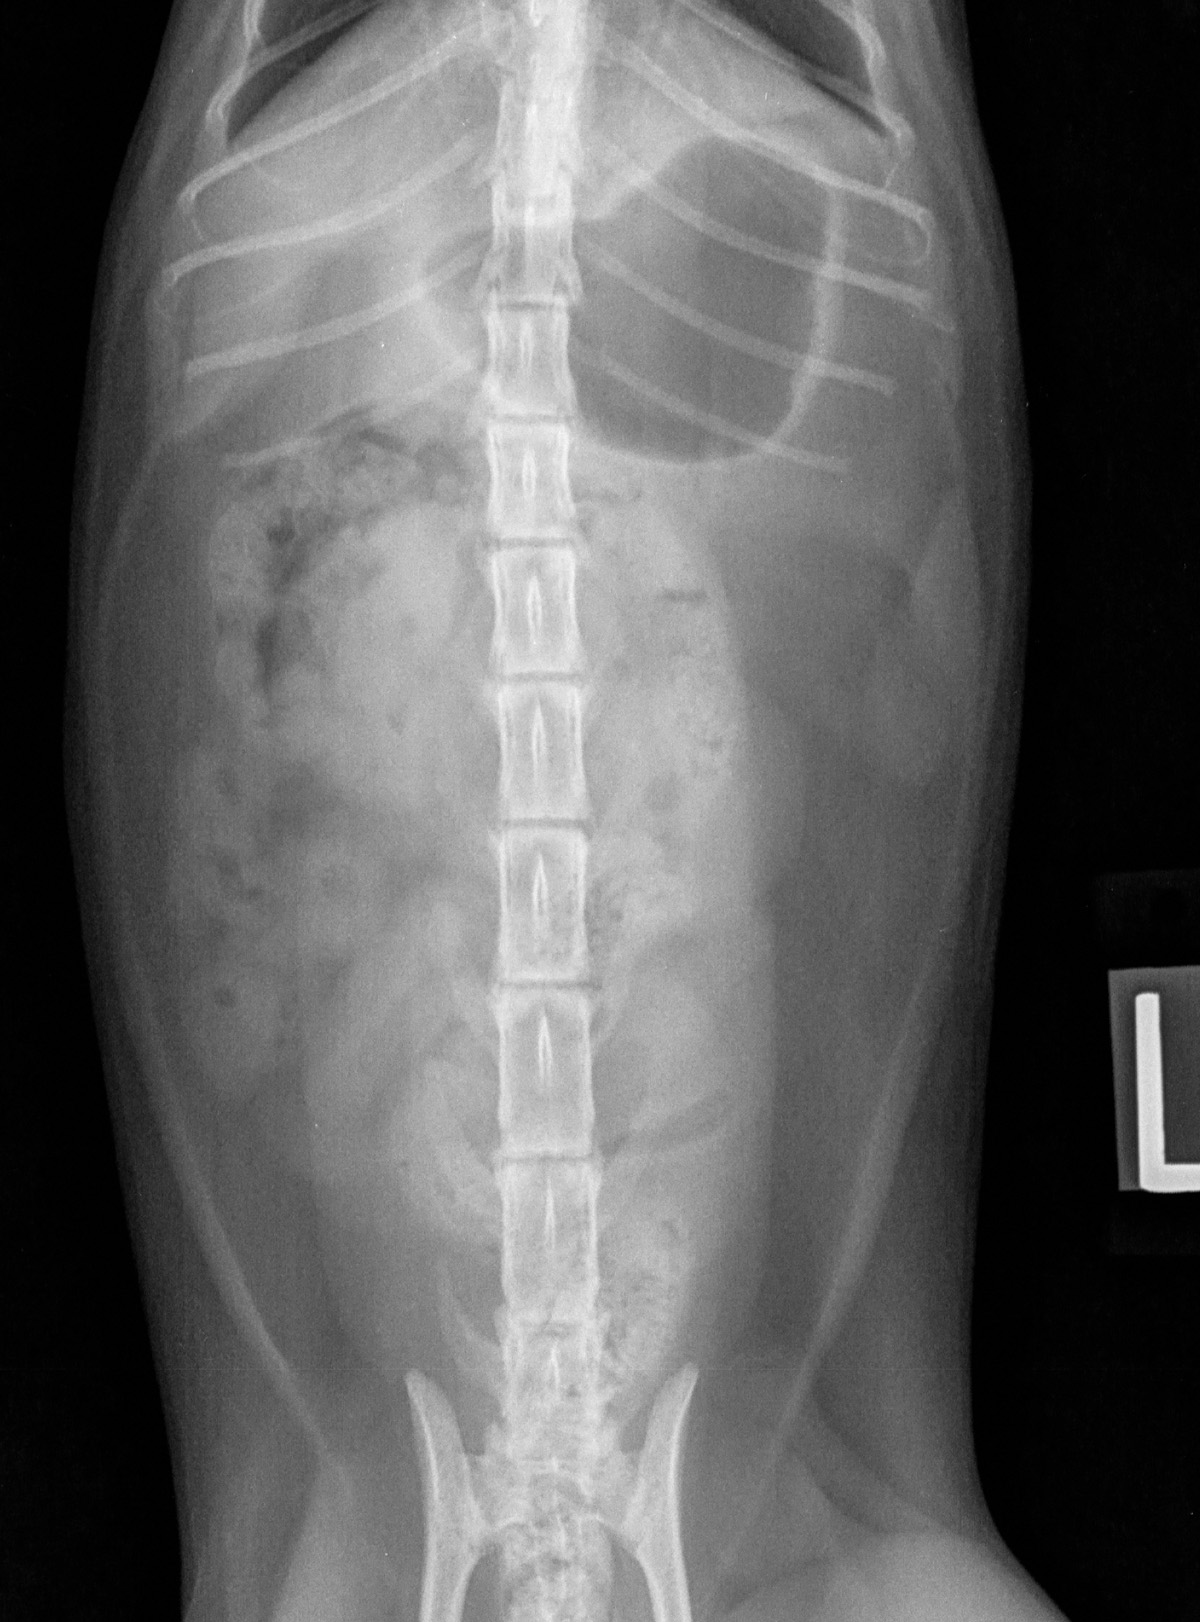

RadioQuiz 13 – Donnez-lui un petit sac

Signalement: chatte domestique stérilisée de 2 ans

Histoire clinique: vomissements aigus depuis 2 jours